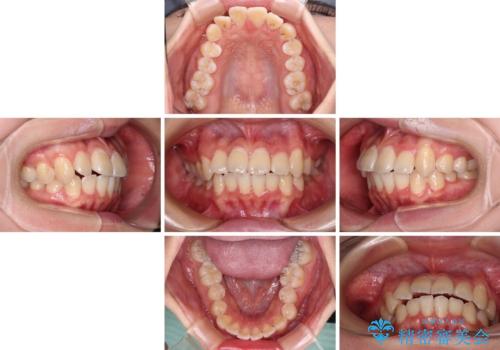

インビザラインでの治療を希望されていましたが、前歯のクロスバイトや下顎小臼歯の捻転が認められたため、インビザライン単独で治療を行うよりも、ワイヤー装置を併用した方が、治療期間の短縮やトラブル回避できると判断し、ワイヤー装置を併用することとしました。

まずはワイヤー装置により前歯のクロスバイトと下顎小臼歯の捻転を改善し、その後インビザラインにより全体を整える矯正治療を行うこととしました。

前歯のクロスバイトは、インビザラインでの改善中に前歯に過剰な力がかかり、歯髄壊死や歯肉退縮を引き起こすことがあります。また下顎小臼歯は寸胴型のため、捻転を排除することが難しいことが知られています。

それをワイヤー装置にて速やかに改善することで、トータルでの治療期間を短くすることができます。